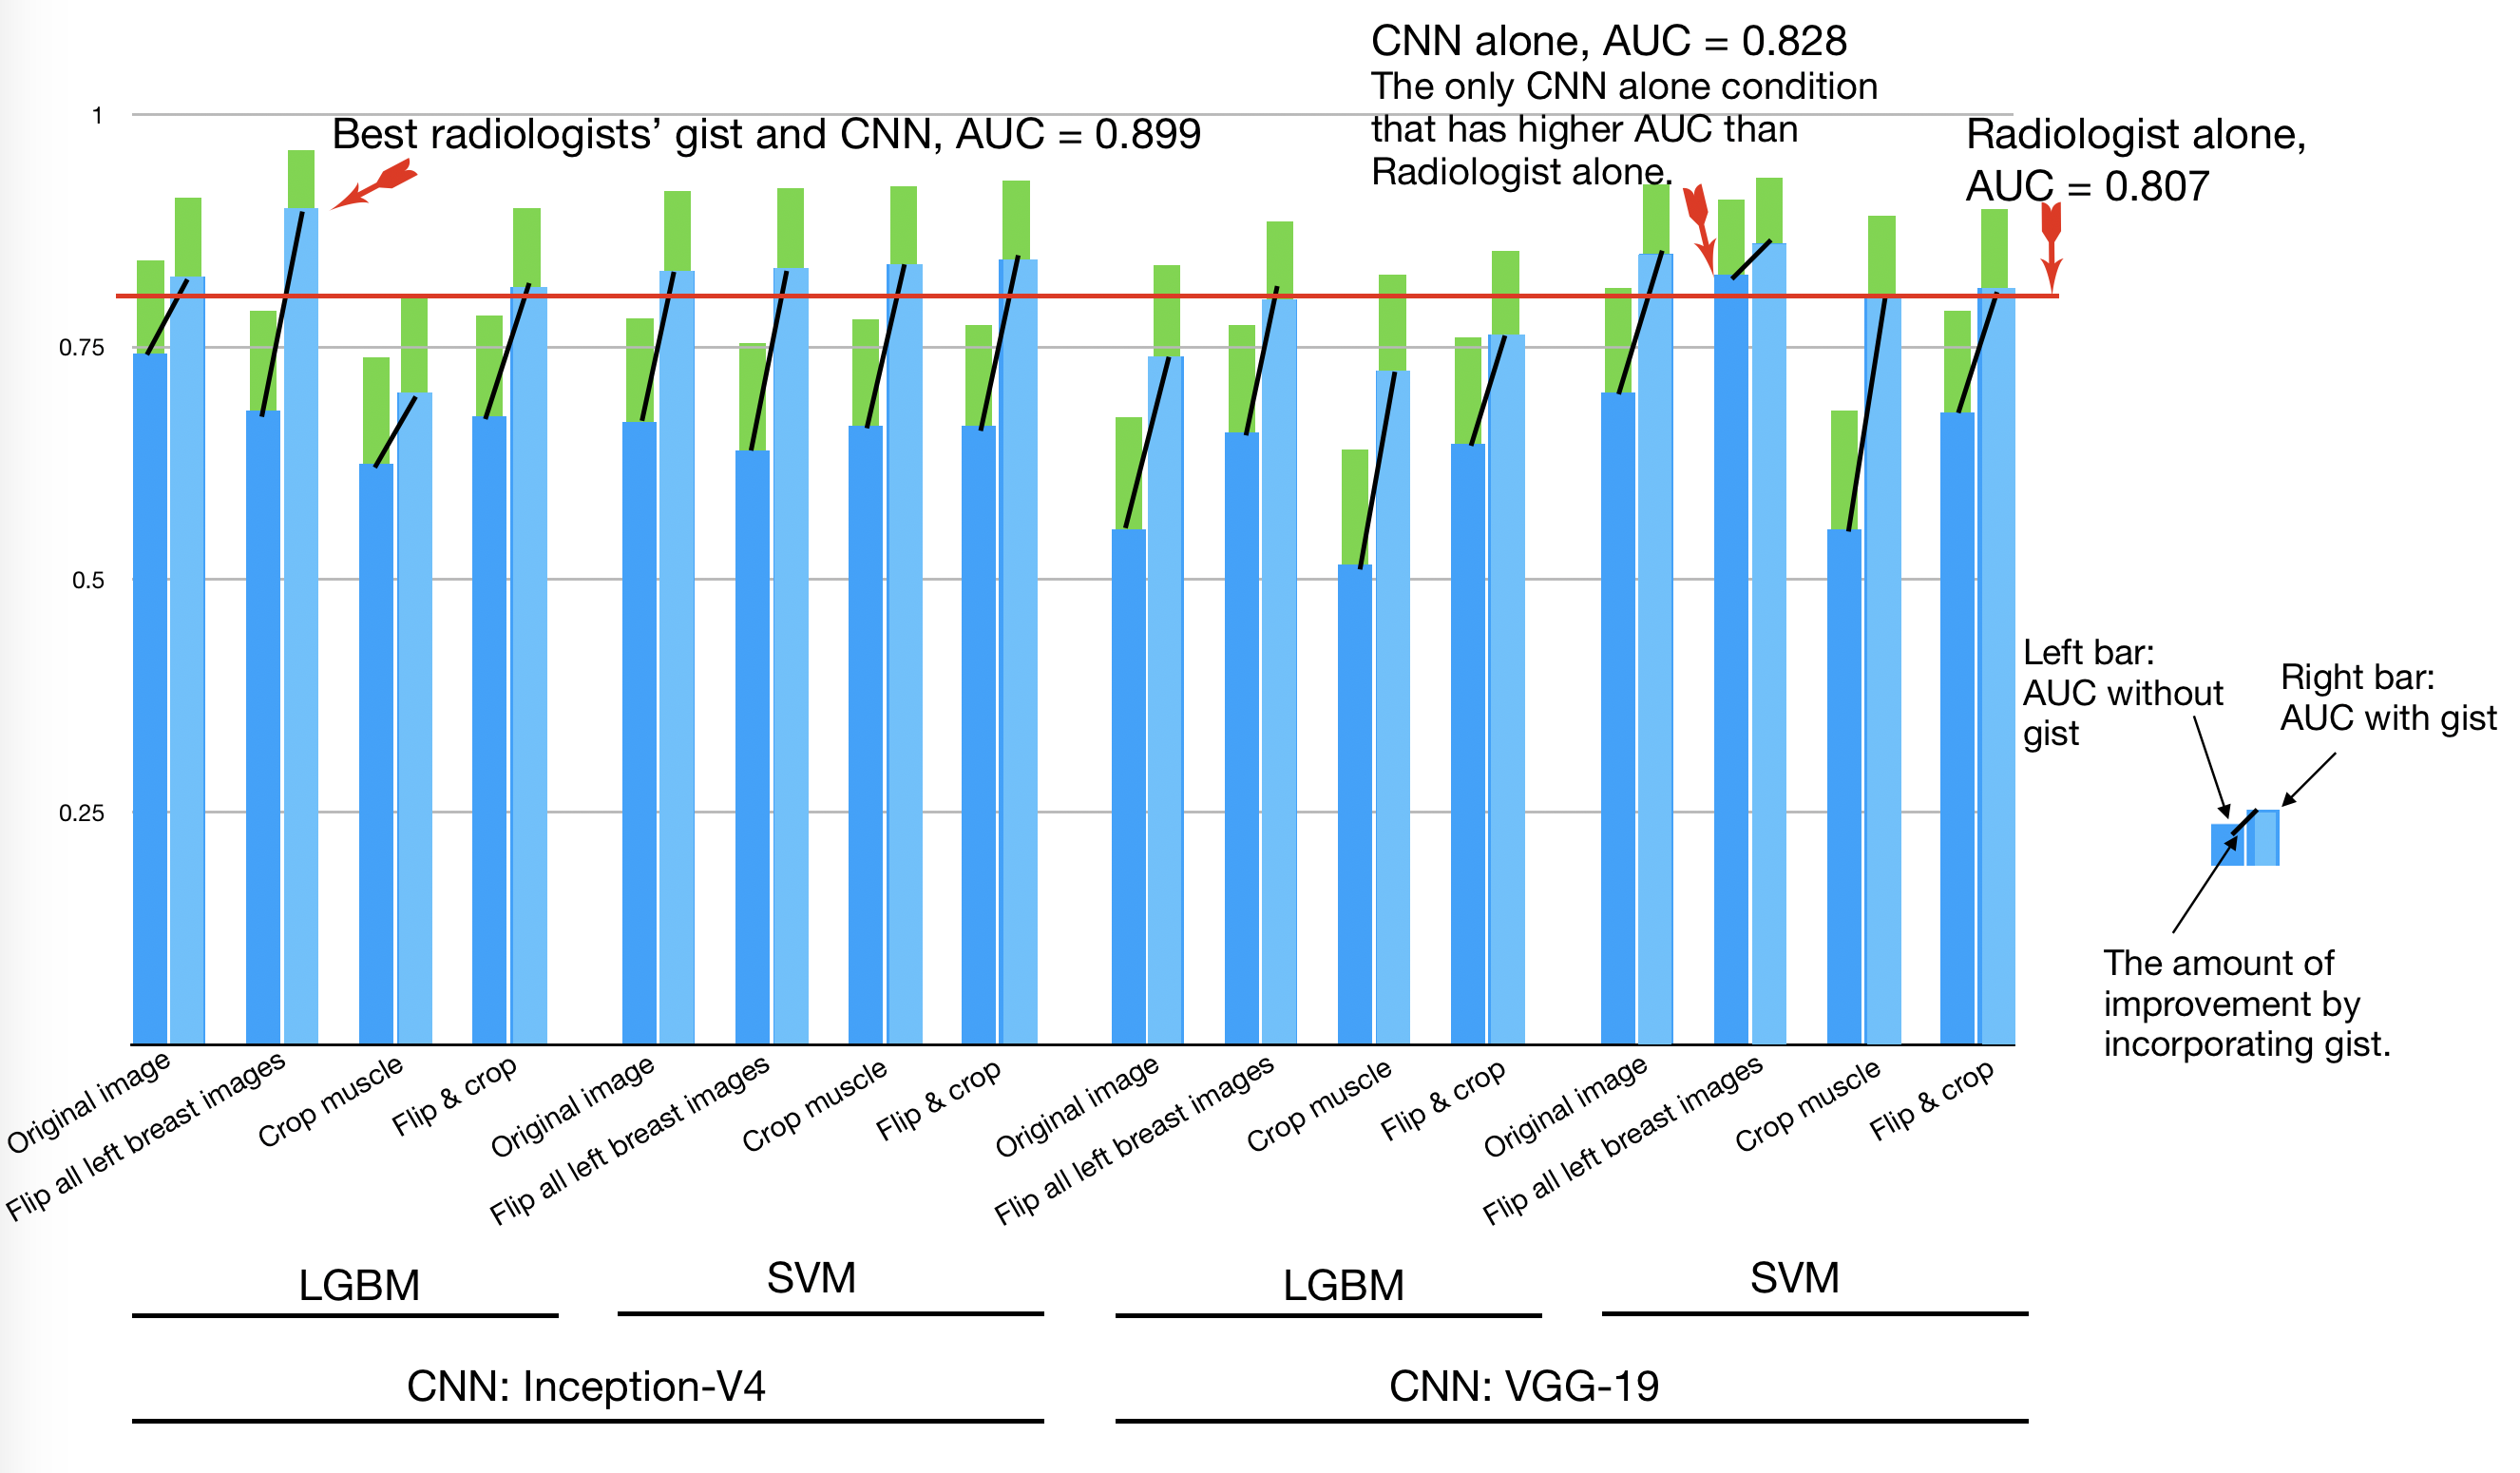

Our baseline condition (A) is the radiologists-alone condition in Evans et al. [5] (Figure 1 lower-left): radiologist gist data are gathered by showing radiologists a unilateral mammogram of a mammogram image with no abnormalities, an image with an abnormality, or an image contralateral to an image with an abnormality for 500 milliseconds each. They perform at an above-chance level at classifying abnormal and normal mammograms in our dataset, with an accuracy of and an area under the receiver operating characteristic curve (ROC and AUC) of 0.81 (Figure 2).

Our baseline condition (B) is the CNN-alone condition, when classifiers do not use radiologist gist response in the input vector (Figure 1 lower-right and AUCs in Figure 2, darker blue bars). Our end-to-end models on average achieve an AUC of 0.656. Also, only one of the resulting AUCs (AUC = 0.828) from these 16 CNN-alone classifiers is better than the radiologist baseline of 0.809. The confidence interval (CI) is ) with the following system: preprocessing option 2 on inputs (input images facing the same direction), fed through VGG-19 for the features, and finally classified with a linear SVM. We think overall this CNN-is-largely-worse-than-human may be due to our dataset being relatively small compared to other mammogram screening datasets.

Our new systems are to combine the baseline condition (B) with the radiologists’ input (Figure 1 top and AUCs in Figure 2 lighter blue bars). We see substantial improvements to the baseline B models when we add radiologist gist response into the classifier’s input in CNNs, with these new classifiers outperforming radiologists in some cases. The average AUC of the 16 classifiers increases to 0.814. On average, each classifier improves its AUC by 0.157, reduces the false positive rate (FPR) by 0.188, improves the true positive rate (TPR) by 0.101, and improves accuracy by 0.144. In all cases, AUC, accuracy, true-positive rate (TPR), and false-positive rate (FPR) improve when adding radiologist gist response to the input vector, except for one that had a small decrease in TPR. In 10 of the 16 classifiers that use radiologist gist response in the input vector, we observe an AUC higher than the radiologists’. One result reports an AUC of 0.899, achieved with preprocessing option 2 (flip all left breast images) before feeding the inputs to Inception-v4 for the feature vector and then using LGBM for classification. Further, this stand-out case from our tests approaches the AUC of specifically trained deep network for the same task [10].

We further analyze this most successful classifier’s results before and after adding the radiologist gist response to the input vector. We notice interesting trends when comparing the radiologists’ decisions to the classifier’s decisions. The classifier utilizing both the deep features and the radiologist gist input manages to correct 8 of the 16 false negative errors that the radiologists made, while only introducing three false positives and one false negative. On the other hand, after introducing the radiologist gist input to the classifier, 25 errors made by the classifier without gist response input are corrected, with only three errors introduced. These corrections include 8 false negatives and 17 false positives. There are also 5 instances in which both the classifier and the radiologists make the same mistake (see Supplementary materials for these image samples). In this same case, we see an improvement over the classifier not utilizing radiologist gist response, increasing AUC from 0.681( CI [0.558, 0.789]) to 0.899( CI [0.823, 0.962]). One-way Welch’s F test shows a statistically significant main effect of the classifier on the AUC ( = , ). A Games-Howell post-hoc test revealed that the AUC of the classifier without gist input is statistically significantly lower than the radiologists’ gist response (0.679 +/- 0.0597, ), and that the classifier with gist input was statistically significantly higher than the radiologists’ gist response(, ).